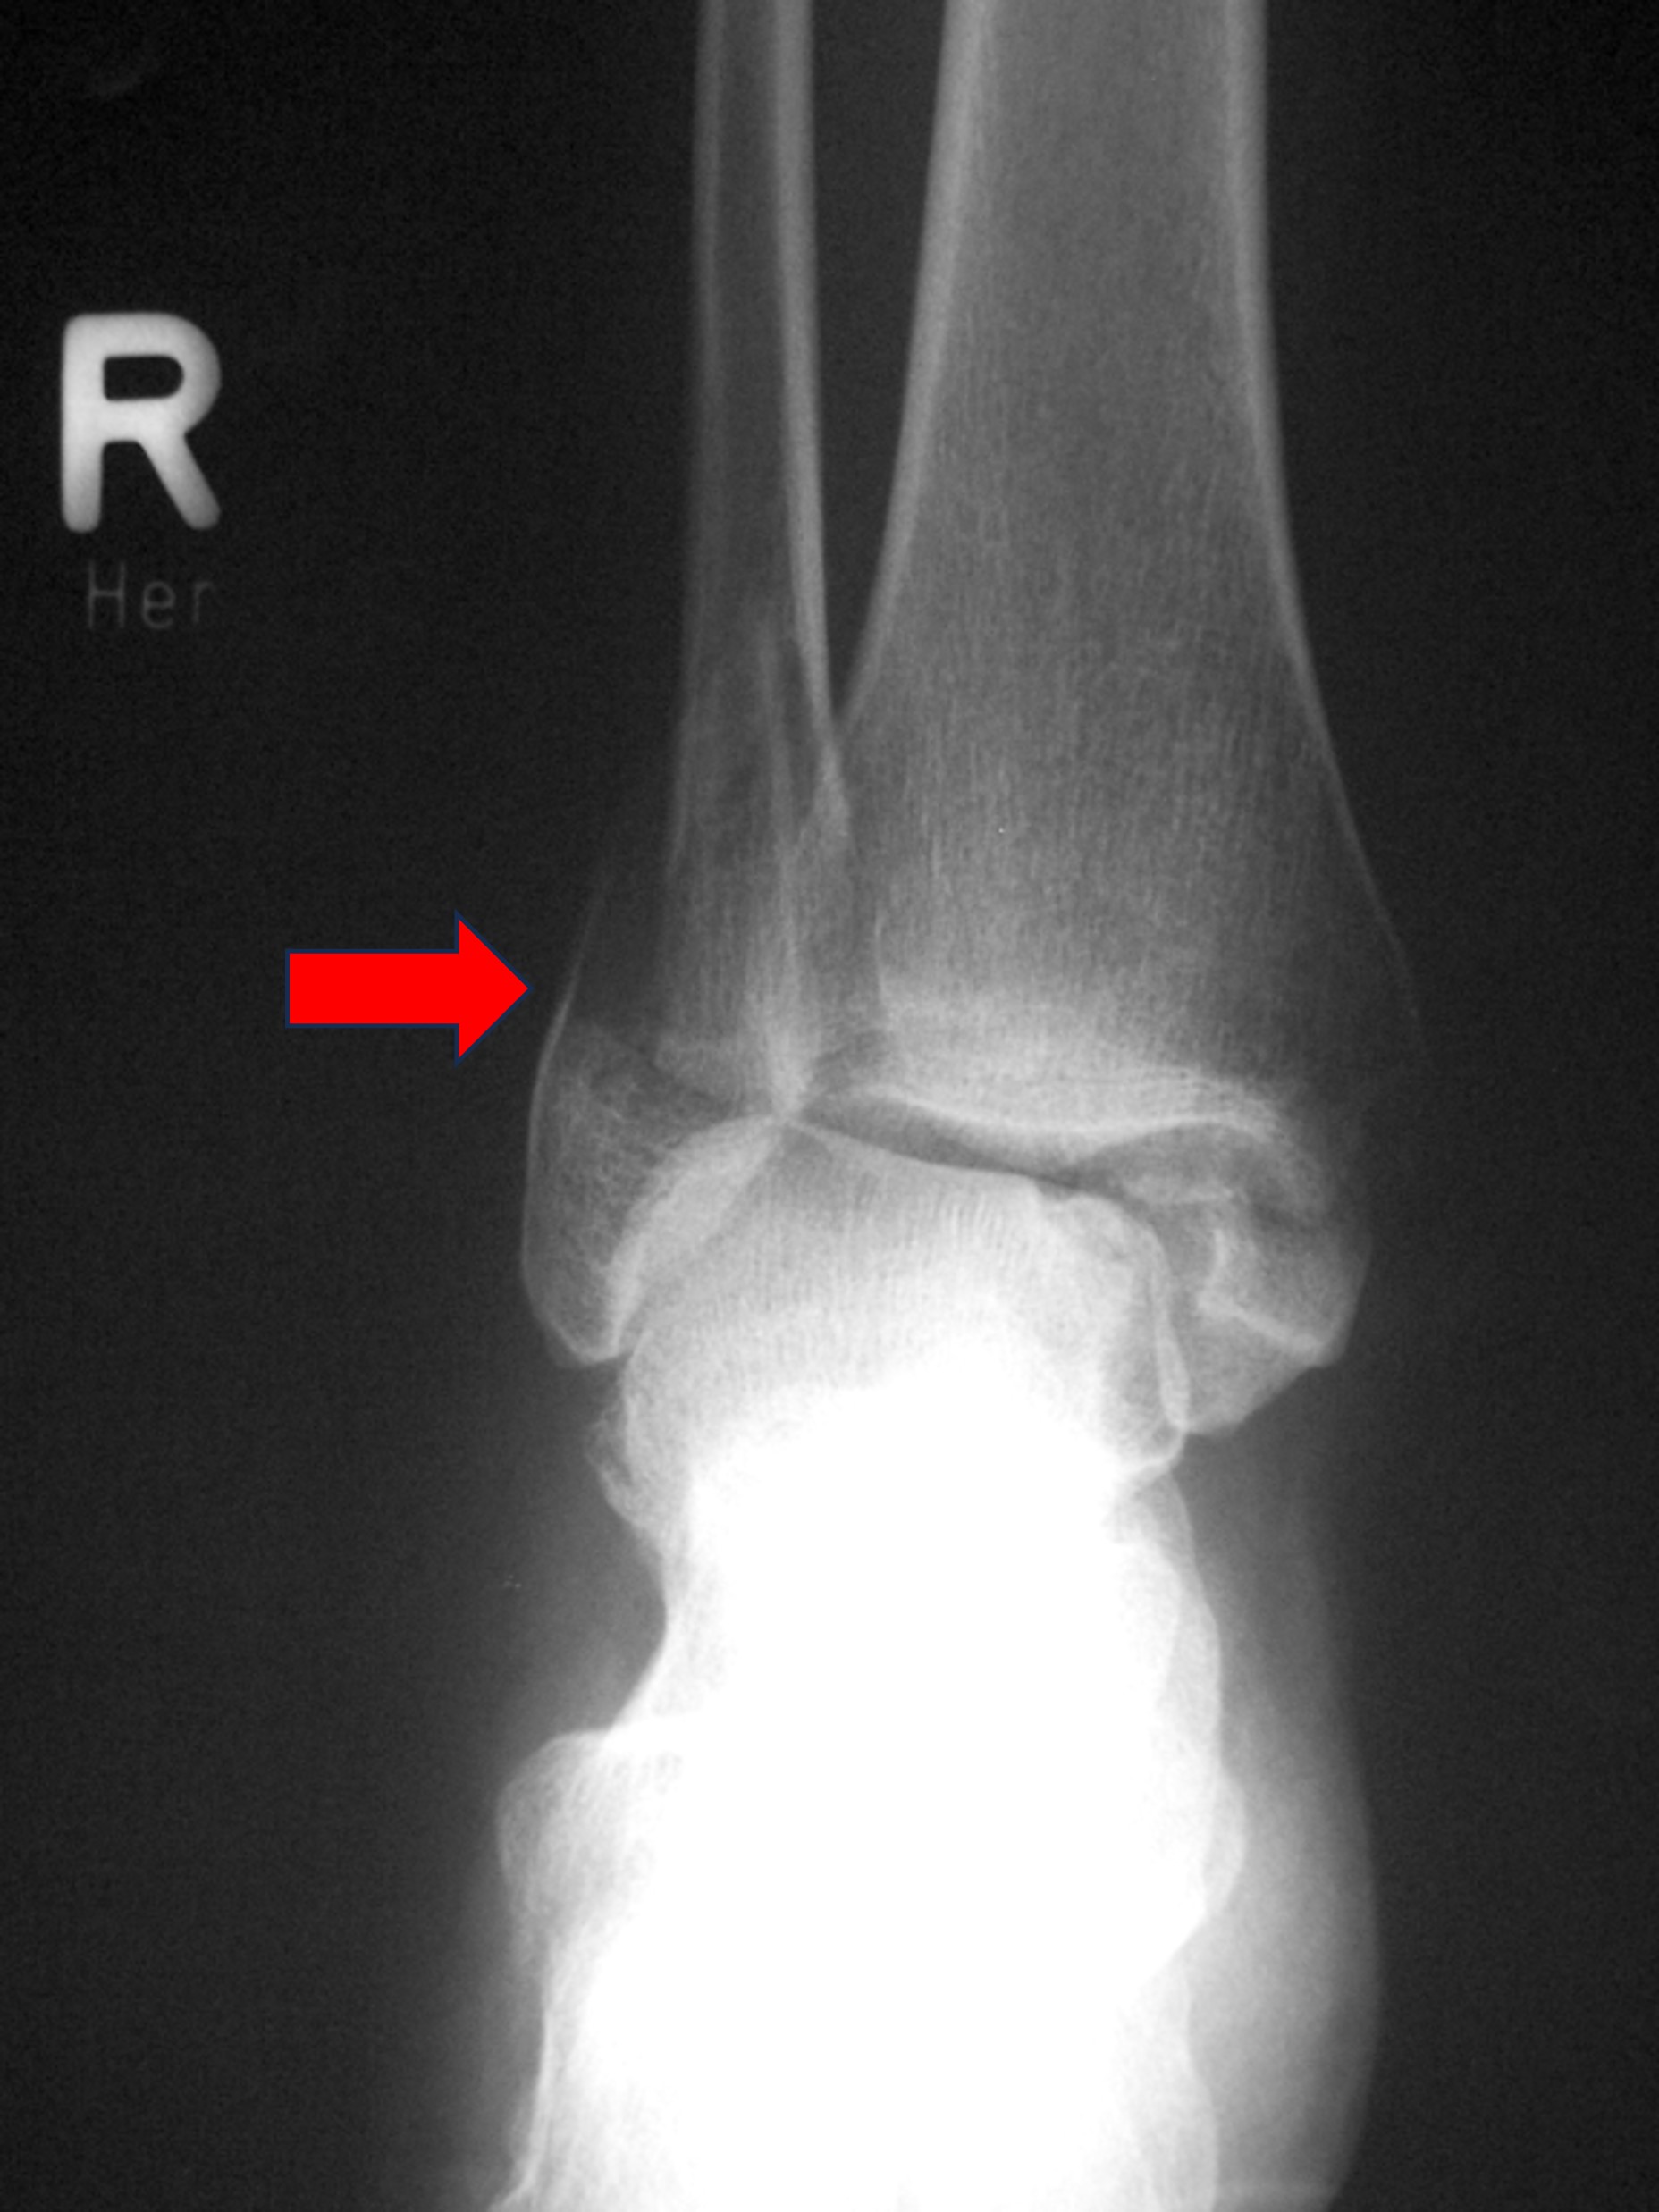

발목 염좌에서 X-ray는 아주 중요한 역할을 하는데요, 바로 골절을 감별해주기 때문입니다. 생각보다 일상생활에서 발생한 발목 염좌로 인해 병원에 오신 분들 중에서, 골절이 동반되는 경우가 많이 있습니다. 격한 운동을 하지 않았더라도, 본인의 체중이 발목에 온전히 실린채로 넘어지거나 미끄러지는 경우에, 하이힐을 신거나 게단을 내려오던 중에도, 골절이 발생하는 경우가 있습니다. 불완전 골절이나 골절 자체가 흔히 말하는 '금만 간 골절'인 경우, 다시말해 골절편의 전위 (어려운 말이죠)가 없는, 또 쉽게 말하자면, '뼈는 부러졌지만 부러진 뼈조각이 원래 자리에서 벗어나지 않은' 골절이라면 X-ray로 진단 후에 석고 부목으로 고정을 함으로써 비수술적 치료를 시도할 수 있습니다.

하지만 X-ray상에서 골절된 뼈가 원래 위치에서 벗어나있는 경우에는, 요즘은 대부분 빠른 일상생활로의 복귀와 추후 발생할 합병증을 최소화 하기 위해, 수술적 처치를 하게 됩니다.

이러한 중요한 결정을 해야할 수 있으니, 초기에 정형외과를 방문해서 X-ray를 꼭 찍어보는 것이 중요합니다. 골절이 된 것을 놓치고 추후에 발견하게 되면, 그 사이에 뼈는 자기들끼리 붙으려고 노력을 하게되고, 골진이 나와 추후 수술을 더욱 어렵게 만들 수가 있습니다. 심한경우에는 삐뚫게 붙은 뼈를 다시 인공적으로 골절시킨 후에 원래 정렬을 맞춰야 하는 경우도 있습니다.